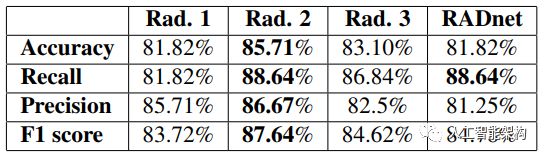

对于要为临床应急设置部署的任何自动化系统,需要可靠的估计以及对人类专家水平的高度敏感性。我们将算法的性能与现实世界放射科医师的判断结果进行了比较。在77个脑CT的数据集上测量了三名高级放射科医师和RADnet的表现。RADnet在CT水平上的出血预测准确率为81.82%,与放射科医师相当。结果显示在此表中:

与三位放射科医师中的两位相比,RADnet的Recall率更高,这是非常了不起的。